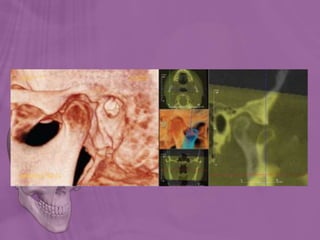

TMJ Degenerative Changes

• Conventional tomography has been used extensively for the evaluation of TMJ hard

tissues; however, technique sensitivity and the length of the examinations made it a

less attractive diagnostic tool for the dental practitioner.

• CBCT images of the TMJ have been shown to provide greater reliability and

accuracy than tomographic or panoramic views in detecting condylar erosions.

• With temporomandibular dysfunction continuing to be a haunting pathology in some

orthodontic cases, it is important to view the anatomy of these patients’ joints

carefully before, during, and after orthodontic treatment.

• Current software solutions allow the visualization of TMJ osseous elements isolated

(segmented) from other surrounding structures.